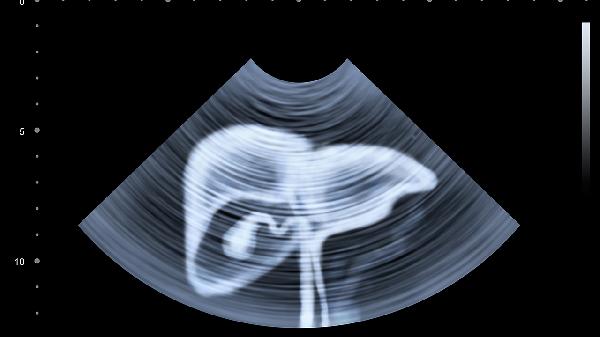

2、影像学检查结构检查

B超是肝脏影像学检查的首选方法,通过无创检测可显示肝脏大小、形态、回声等,帮助判断是否存在脂肪肝、肿瘤或肝硬化早期迹象。对于疑似肝纤维化或结节,磁共振成像MRI和计算机断层扫描CT具有更高的分辨率,建议进一步确认。不吸烟、无肝病家族史的年轻人可首选B超,重度脂肪肝或高危人群推荐年度MRI筛查。